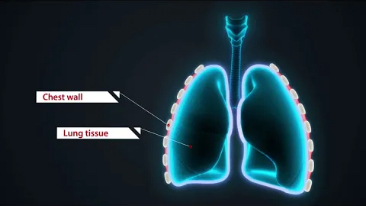

??? ??? ? ??

Mindray? ??? ??? ?? ??? ???? ??? ?? ??? ??? ????? ??? ????. ?? ???? ZONE Sonography? ??? ???? ?? Resona 7? ??? ZST+ ???? ?? ?? ? ?? ??? ????? ?? ??? ??? ??? ? ?? ????.